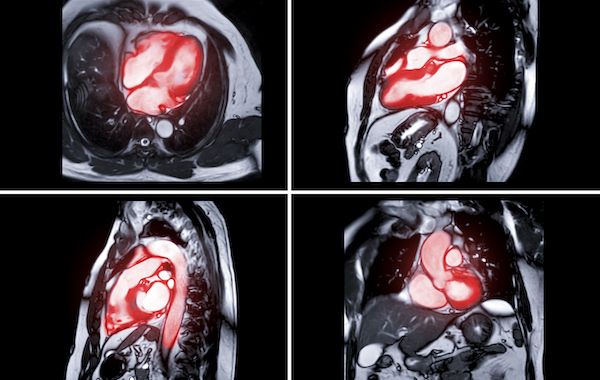

and care of special populations. Sessions will feature interactive Heart Team case discussions, rapid fire clinical cases, and practical workshops in ECG, echocardiography, and multimodality imaging.